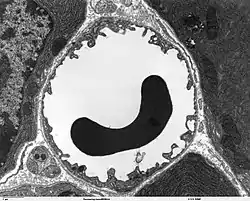

Les cellules endothéliales sont complètement entourées par une couche protéique, la lame basale[5]. Cette double couche épaisse de 40 à 50 nm n'est visible qu'au microscope électronique. Elle est constituée essentiellement de collagène de type IV, de protéoglycanes-héparan-sulfate, de laminine, de fibronectine et autres protéines de la matrice extracellulaire. Cette lame basale touche la membrane plasmatique des pieds astrocytaires[7],[24].